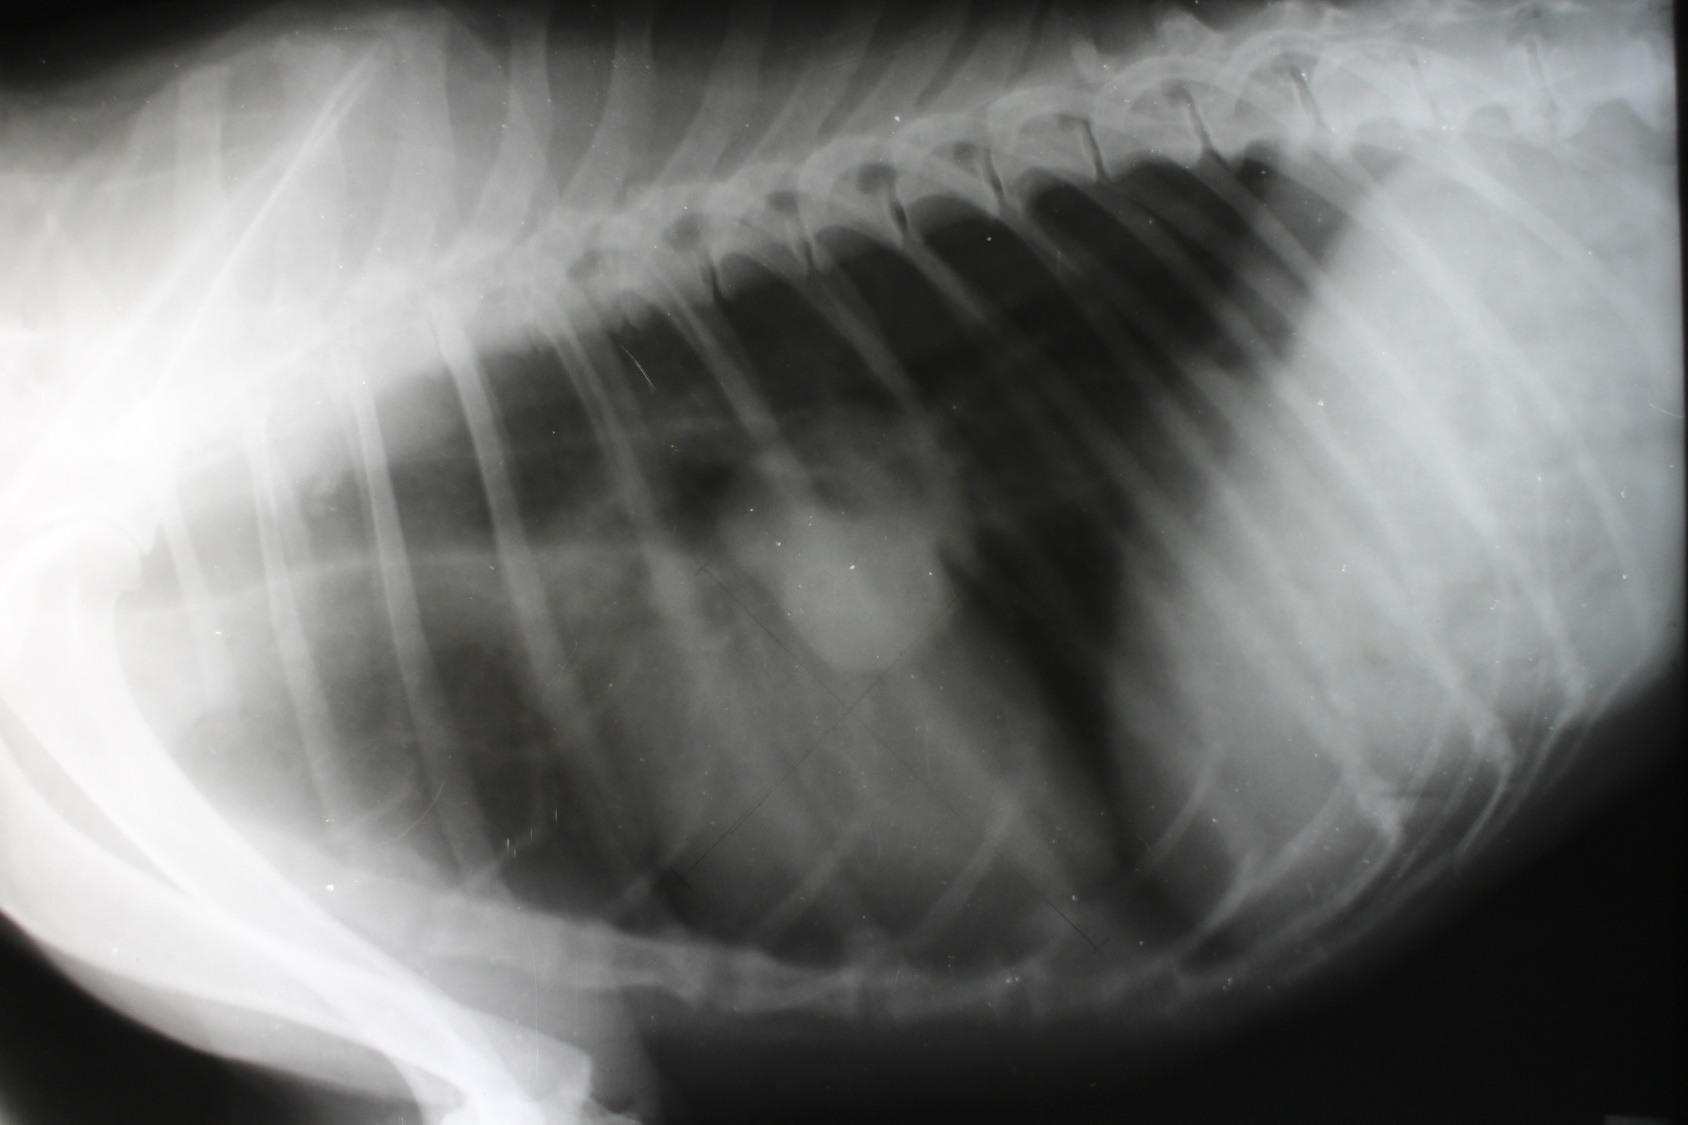

- Cirugía de pequeños animales

Clínica Veterinaria Chisperos ofrece un amplio rango de servicios veterinarios, incluyendo ultrasonido, terapia física, rehabilitación, laboratorio en el local, oftalmología, odontología, cirugía de pequeños animales y exóticos, medicamentos prescripción, citología, medicina veterinaria de pequeños animales y exóticos, vacunación y identificación (chip), endoscopia, atención telefónica de emergencia, oncología, y medicina preventiva. La clínica está equipada para manejar una variedad de necesidades veterinarias, desde revisiones rutinarias hasta procedimientos especializados, asegurándose de mantener el estándar de cuidado más alto para mascotas y animales exóticos.

Mario, el veterinario de la clínica, es conocido por su experiencia y enfoque compasivo. Se le elogia por sus habilidades quirúrgicas meticulosas, particularmente en la realización de procedimientos complejos con resultados impecables.